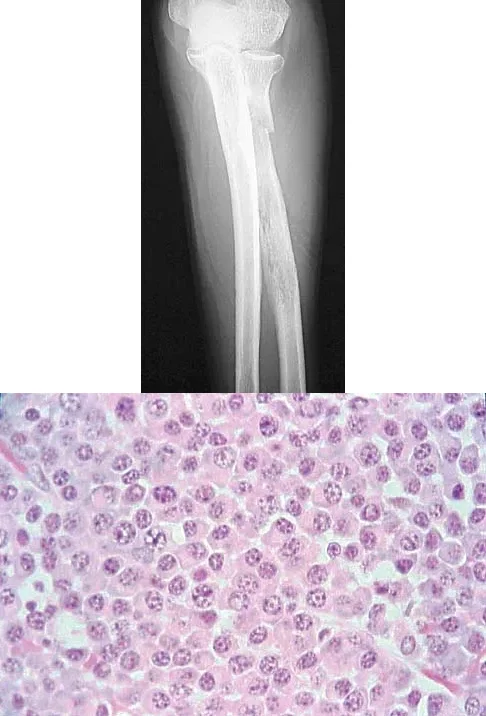

Question 39

A 65-year-old woman presents with chronic aching in her elbow. Radiographs and a biopsy specimen are shown. The histology reveals round to oval cells with an eccentric nucleus, prominent nucleolus, and a clear perinuclear area representing the Golgi apparatus. Which of the following is the most likely diagnosis?

Explanation

Correct Answer: C

The histologic description and image are pathognomonic for plasma cells, which characterize multiple myeloma. The cells are round/oval with an eccentric nucleus, prominent nucleolus, and a perinuclear clearing (halo) that represents the prominent Golgi apparatus. Multiple myeloma frequently presents as lytic bone lesions in older adults.